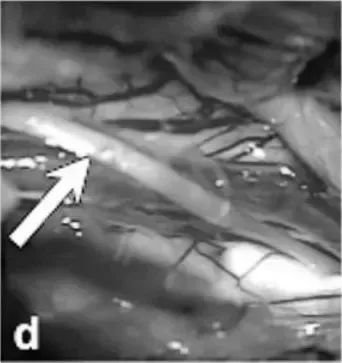

巴教授果斷采取經(jīng)右側(cè)顳下入路實施手術(shù);術(shù)中發(fā)現(xiàn),在滑車神經(jīng)水平,被蓋表面明顯膨隆(箭頭,圖d)。